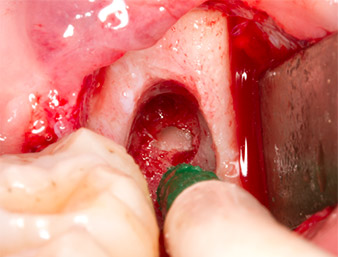

Tras una anestesia local y por conducción, el campo quirúrgico se abrió mediante los tejidos blandos para tener un acceso bucal-retromolar y se dejó expuesto (figura 3).

El tejido situado por encima del resto radicular no se había osificado por completo y constaba en su mayor parte de un tejido granulado con alteraciones inflamatorias (figura 4).